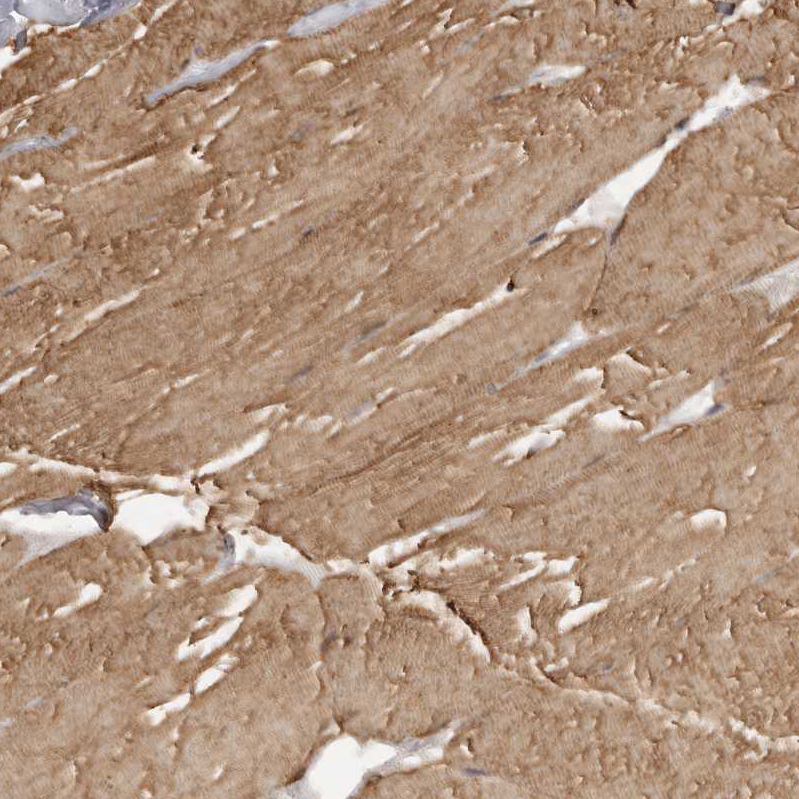

Immunohistochemical staining of human skeletal muscle shows moderate cytoplasmic positivity in myocytes.